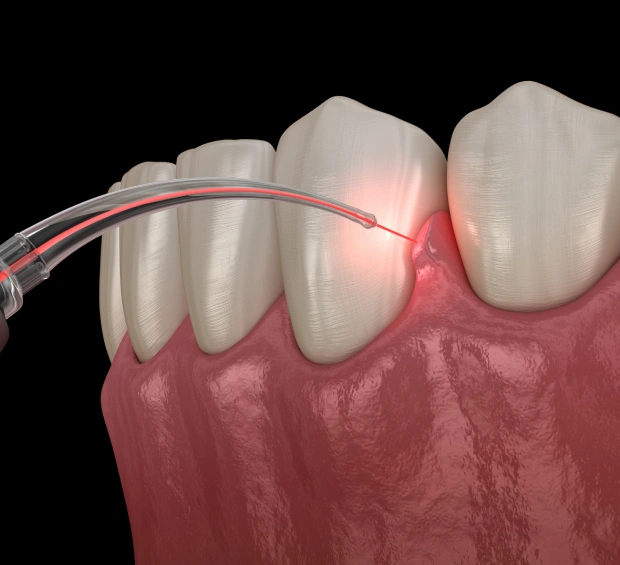

AtKaty Smile Design, we utilize advanced MLS laser therapy to target and reduce inflammation in the affected areas. This non-invasive technology uses synchronized light wavelengths to penetrate deep into the tissue, promoting cellular repair, improving blood flow, and blocking pain signals. The result? Faster healing and significant relief from TMJ pain and other related symptoms.

During an MLS therapy session, your dentist will use a handheld device to deliver light energy to the affected area. The treatment is painless, with most patients feeling only a gentle warmth as the laser works to reduce inflammation and promote healing. Depending on the severity of your TMJ disorder, you may require multiple sessions for optimal results, with most patients noticing significant improvements after 2 to 3 treatments.